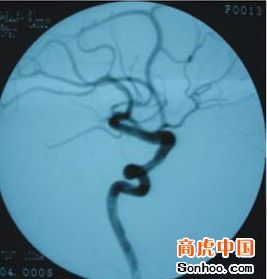

2顱內占位性病變

①頭痛。顱內壓增高時其腦膜、重要的血管神經受牽拉引起。發病初起不典型,重時可逐漸呈持續性,甚至難以忍受。②嘔吐。是腦幹移位和牽拉或腫瘤直接刺激延髓的嘔吐中樞,嘔吐呈噴射性,不伴有其他消化道症狀,常在頭痛劇烈時出現,嘔吐後頭痛稍緩解。兒童因腫瘤常發生在後顱凹,早期即可出現嘔吐,易被誤診為消化道疾病。③視乳頭水腫。顱內壓增高,眼靜脈回流受阻,視乳頭邊界欠清、靜脈充血、滲出或出血。早期視力正常,中晚期因繼發性視神經萎縮而視力逐漸減退。④癲癇發作。是占位性病變刺激皮層產生的異常放電。成年人的癲癇發作往往是占位性病變引起。⑤復視、耳鳴、精神異常。⑥腦疝。是顱內壓增高的晚期併發症。